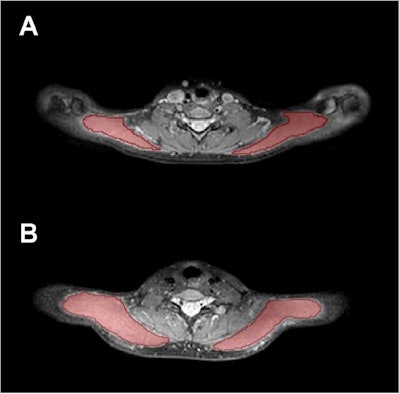

Trapezius muscle segmentations show (A) segmentation masks of the bilateral trapezius muscles (red areas) in a 25-year-old female and (B) in a 24-year-old male. Images and caption courtesy of the RSNA.

In its prospective study, the team included 50 participants. Of these, 16 had tension-type headache and 12 had tension-type headache plus migraine episodes. The groups were matched with 22 healthy controls. The study participants underwent 3D turbo spin-echo MRI and from there, the bilateral trapezius muscles were manually segmented, followed by muscle T2 extraction.